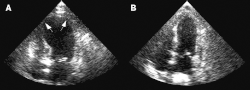

В ходе наблюдения за пациентами часто отмечается выбухание верхушки левого желудочка с гиперкинезом его основания. Картина выбухания верхушки сердца, сочетающегося с сохранённой функцией его основания, дала синдрому японское название тако цубо («ловушка осьминога»)[5].

Диагноз устанавливается на основании патогномоничных изменений подвижности сердечной стенки — нормального сокращения или гиперкинеза основания левого желудочка в сочетании с акинезом или дискинезом остальных его отделов. Это сопровождается отсутствием признаков выраженной коронарной недостаточности, которая могла бы объяснить указанные нарушения сократимости. Хотя классическое ангиографическое описание кардиомиопатии такоцубо включает шарообразное расширение верхушки, встречаются и другие варианты — выбухание межжелудочковой перегородки или, в более редких случаях, выбухание других сегментов[16][18][19][20][21].

Паттерны выбухания были классифицированы Симидзу и др. как тип такоцубо с апикальной акинезией и базальной гиперкинезией; обратная такоцубо с базальной акинезией и апикальной гиперкинезией; перегородочный тип с перегородочным выбуханием в сочетании с базальной и апикальной гиперкинезией; локальный тип с выбуханием других сегментов левого желудочка и клинической картиной такоцубоподобной левожелудочковой дисфункции[19].